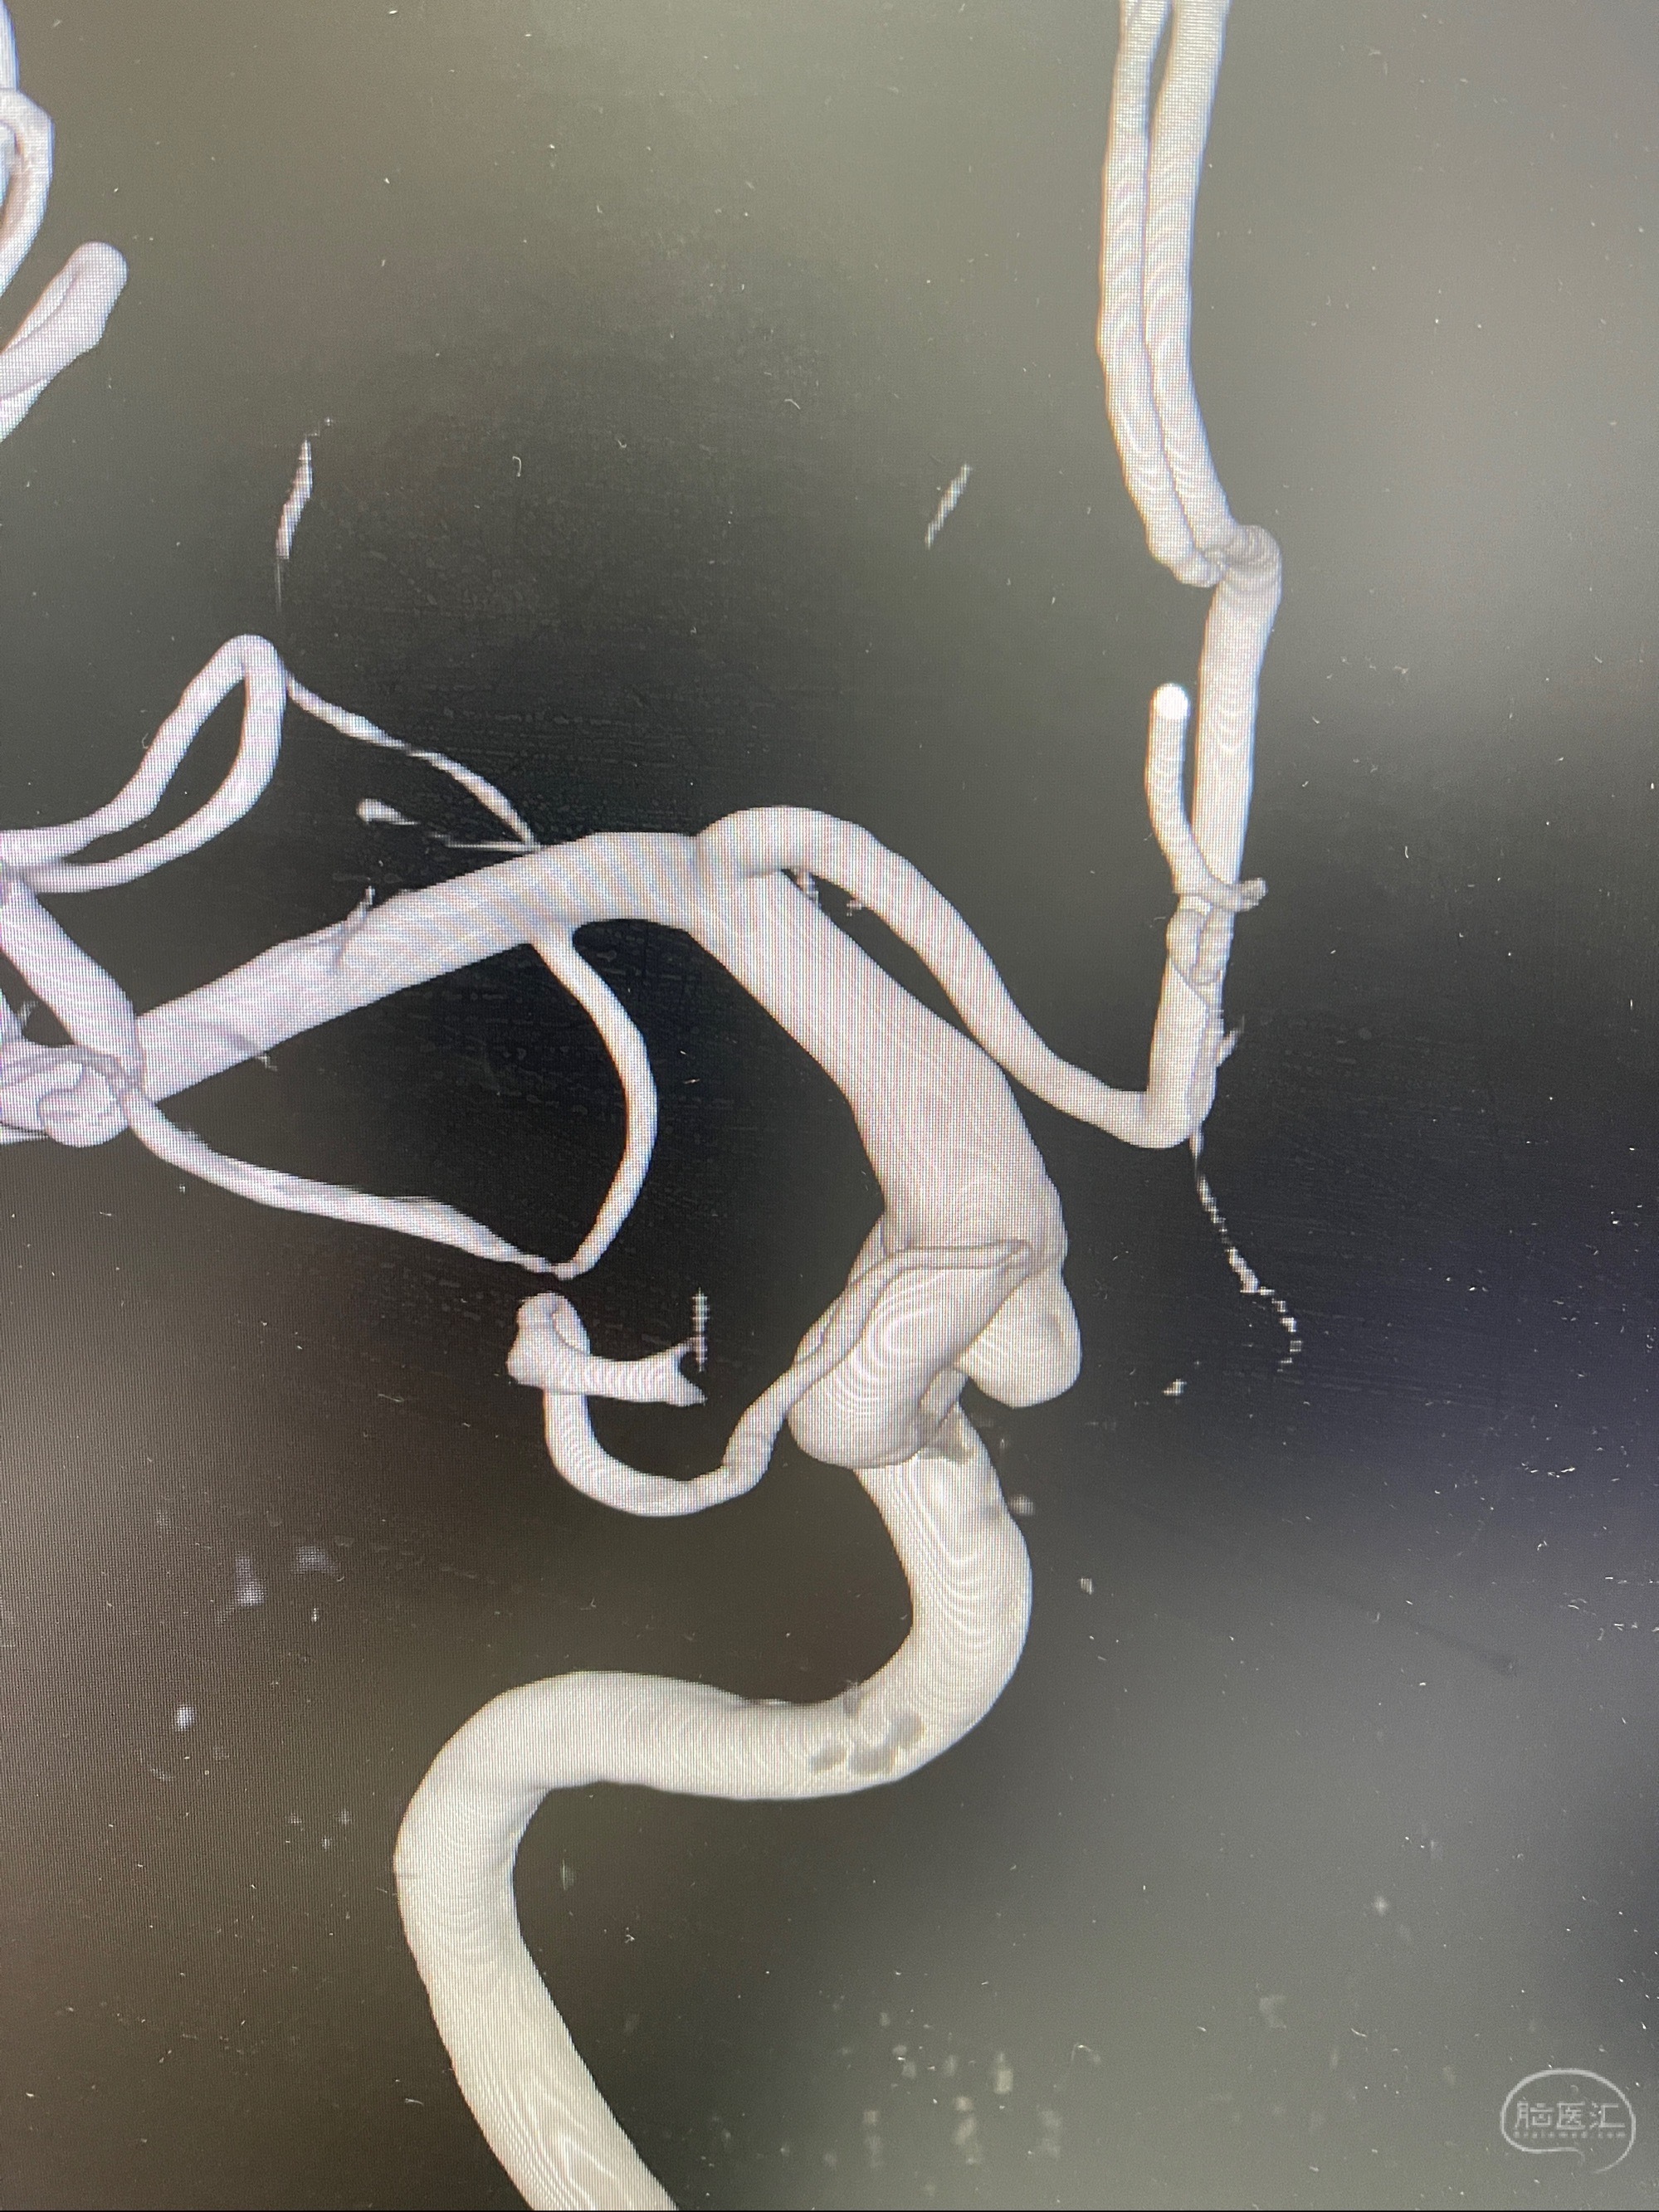

2023.07.25 泰州市人民医院查头颅CTA提示右侧C6段瘤样突起,建议DSA检查;

CTA示:右侧颈内动脉C6段见指向下方的突起,余左侧颈内动脉、双侧椎动脉、大脑前动脉、大脑中动脉、大脑后动脉及基底动脉走形正常,未见明显扩张及狭窄,局部未见明显瘤样扩张。

看原图,应该有两侧动脉瘤😅

2023-07-27全脑血管造影:双侧颈内动脉眼动脉段动脉瘤,右侧较大